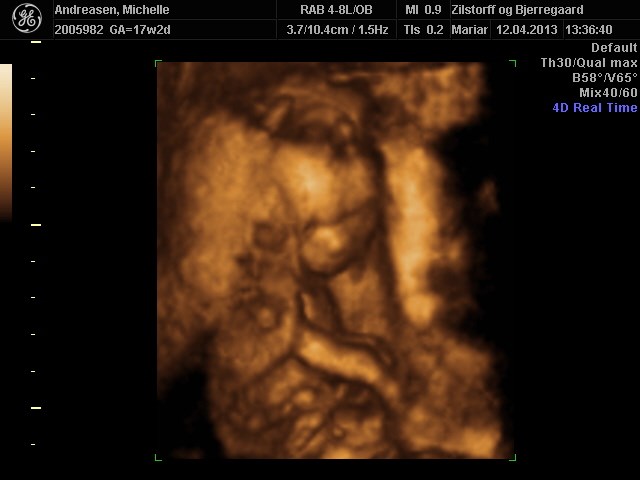

Her er nogle billeder af vores pige 17+2

Vedhæftede fotos (klik for at se i fuld størrelse)